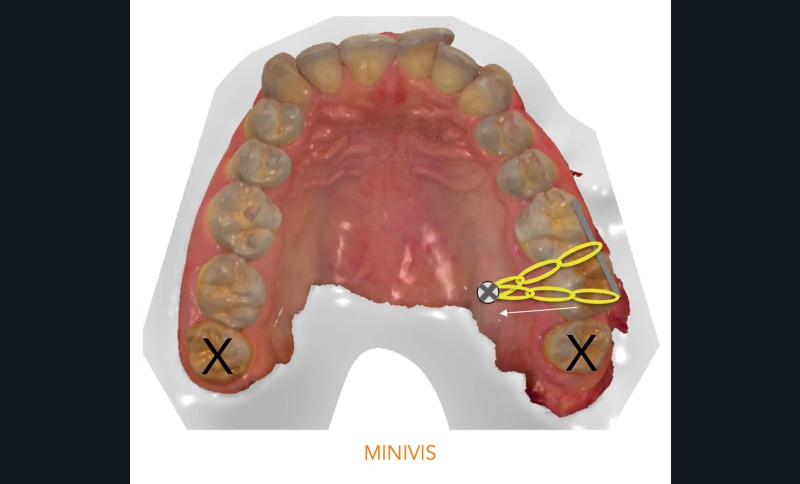

- la première utilisant une minivis pour repositionner sur l’arcade la 27 [1] ;

Dans un premier temps (fig. 2), la 28 (et la 18) a été extraite pour faciliter le déplacement de la 27 (DDM postérieure). Une minivis palatine a été placée entre 26 et 27 et des boutons ainsi qu’un sectionnel collés sur les faces vestibulaires des 26 et 27. Des chaînettes élastomériques ont été ancrées sur les boutons et la minivis, en passant au-dessous des faces occlusales de ces dents. Les chaînettes reliant un dispositif vestibulaire et un palatin et prenant appui sur les faces occlusales des molaires du secteur 2, les mouvements dentaires induits sont un déplacement vestibulo-palatin associé à une ingression des 26 et 27. Les minivis sont des ancrages absolus qui ne nécessitent pas d’utiliser l’ancrage des dents adjacentes ou antagonistes, ce qui préserve d’effets sur ces dernières.